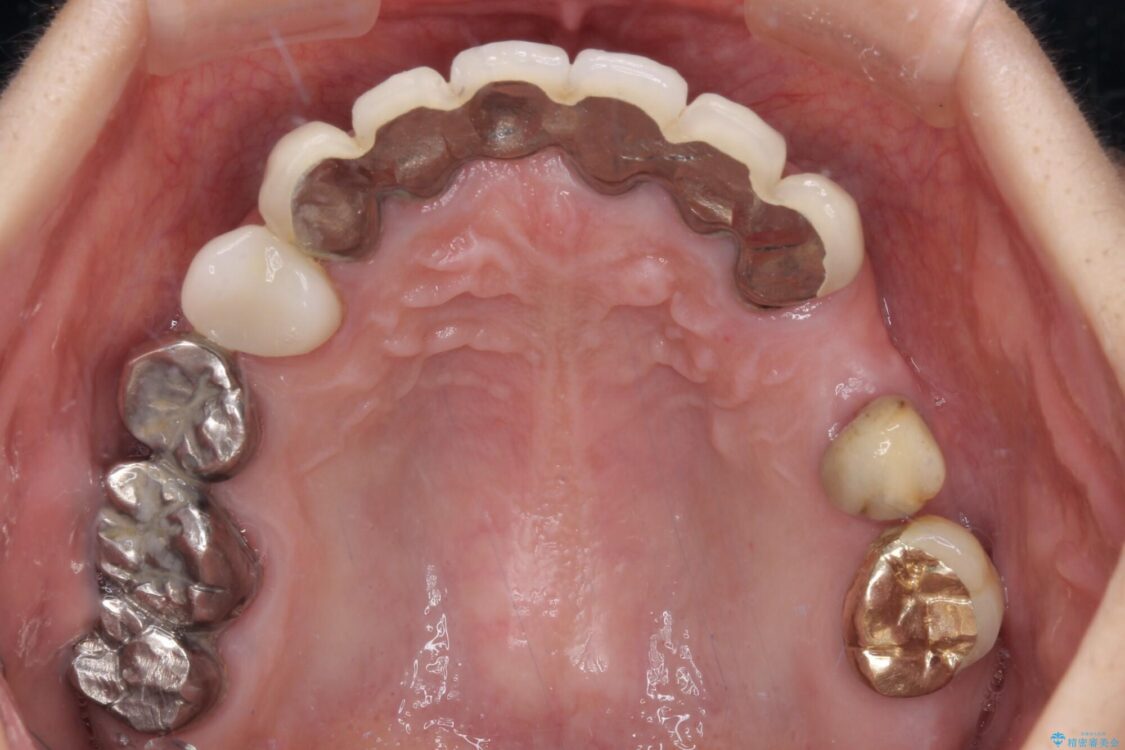

治療前

• 放置したインプラントとインビザライン 全顎リカバリー治療 治療前画像